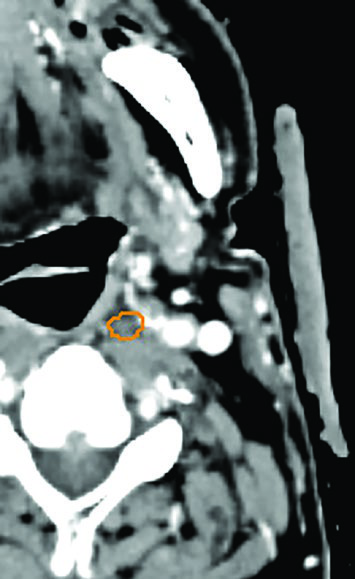

Dental fillings that create artifact and compromise target visualization should be removed before SBRT. A reported case exemplifies this problem well: an 87-year-old frail gentleman with an MRI-incompatible pacemaker had severe artifact from a dental filling that severely impacted target visualization in the left mandibular gingivobuccal sulcus. Tooth extraction made GTV delineation possible. Alternatively, metal fillings can be replaced with non-metal materials prior to simulation.